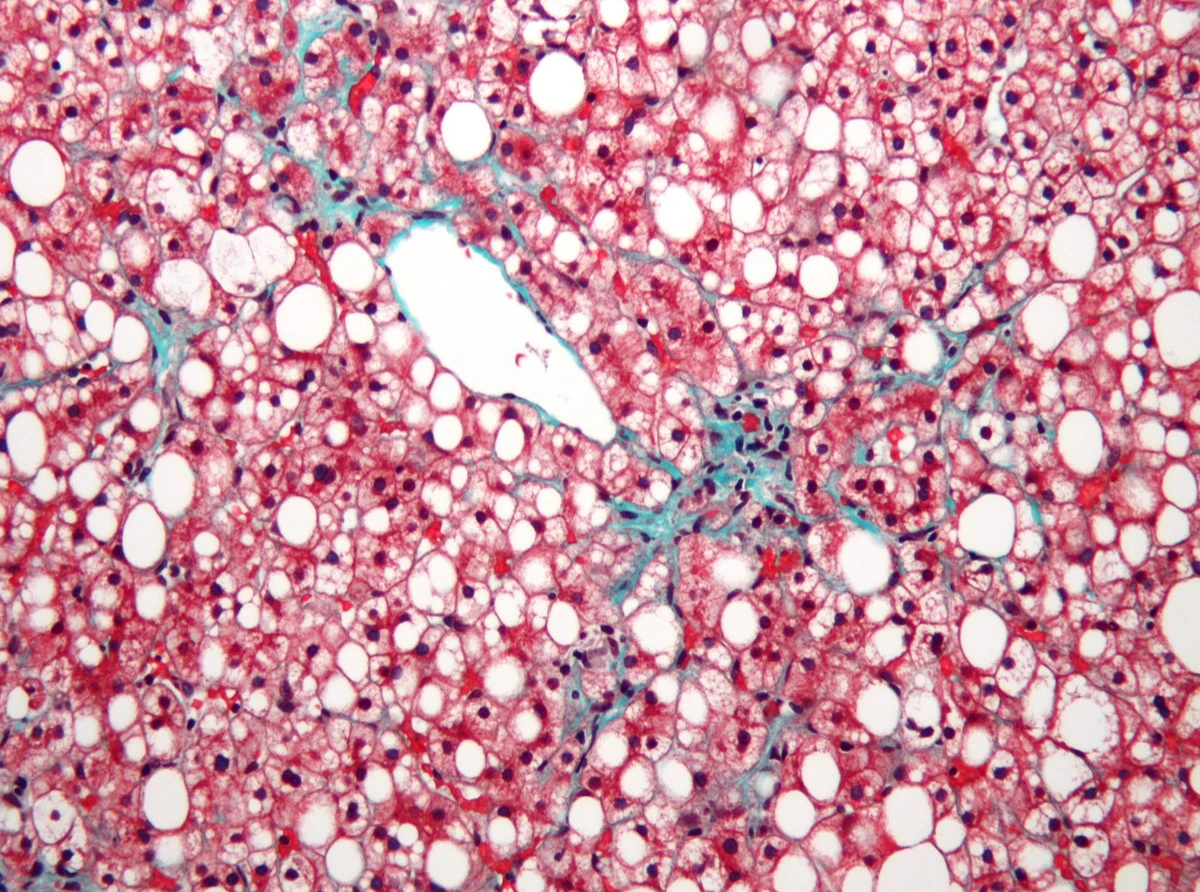

Možná to znáte taky – stačí pár let ne úplně vzorné životosprávy, občasný stres zajedený něčím tučným a doktor vám při kontrole oznámí, že vaše játra začínají připomínat „ztučnělou paštiku“. Jde o problém, který dnes trápí skoro třetinu dospělých Čechů, a co je nejhorší, zatím na něj nemáme žádný zázračný lék v pilulce.

Většina z nás si myslí, že kanabinoidy fungují jen přes receptory v mozku nebo v trávicím traktu. Ale tady přišlo překvapení. CBD a CBG totiž fungují jako jakýsi „energetický restart“ pro jaterní buňky. Stimulují produkci fosfokreatinu, což buňkám pomáhá lépe hospodařit s energií a efektivněji „uklízet“ nashromážděné tuky.

I když je CBD v českých e-shopech a lékárnách k dostání na každém rohu, studie ukázala, že CBG bylo v boji s tukem ještě o krok napřed. Výrazněji snižovalo „špatný“ cholesterol a pomáhalo s úbytkem tělesného tuku u subjektů s vysokokalorickou dietou.